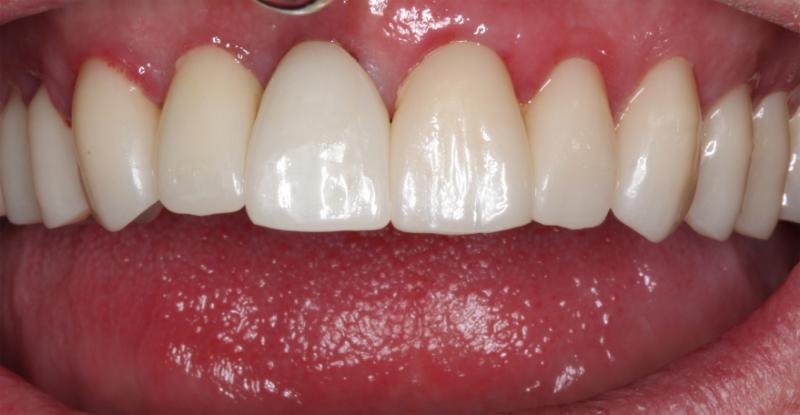

A dental implant is a small titanium post that is surgically placed into the jawbone, providing a foundation for a replacement tooth or teeth. Placing an implant is a common surgical procedure performed by our highly trained prosthodontist.

Dental implants offer incredible benefits, including improved oral health, increased confidence, and better functionality and comfort when compared to traditional dentures or bridges.

The implant process can vary depending on your individual needs and circumstances. In most cases, we can plan, create, and place your implants from start to finish in just one day!